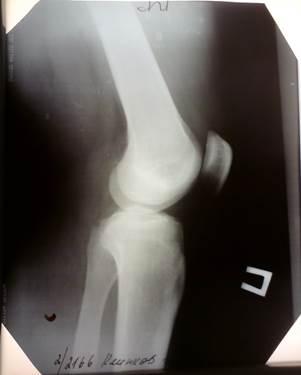

Рентгенограмма правого коленного сустава в двух проекциях

от 22.09.2010г.:

Форма сустава не изменена. Контуры четкие. В боковой проекции наблюдается затемнение костных структур, в связи с отеком. Межмышечные пространства расширены, в связи с отеком мягких тканей.

Боковая проекция

Прямая проекция

4) результатов дополнительных методов исследования: Рентгенограмма правого коленного сустава в двух проекциях от 22.09.2010г.: форма сустава не изменена. Контуры четкие. В боковой проекции наблюдается затемнение костных структур, в связи с отеком. Межмышечные пространства расширены, в связи с отеком мягких тканей.